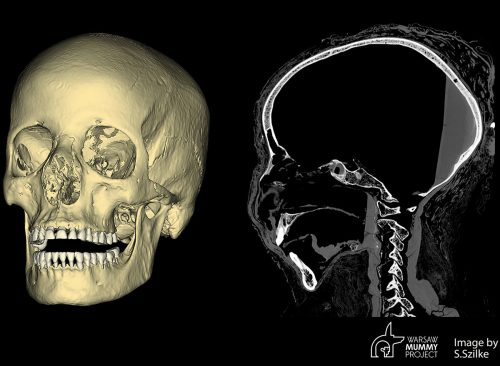

Researchers from the University of Warsaw, aided by two forensic specialists, used 2D and 3D techniques to reconstruct her face. "Facial reconstruction is mainly used in forensics to help determine the identity of a body when more common means of identification such as fingerprint identification or DNA analysis have drawn a blank," said forensic artist Hew Morrison.

"Reconstructing an individual's face from their skull is often considered as a last resort in an attempt to establish who they were. It can also be used in an archaeological and historical context to show how ancient people or famous figures from the past would have appeared in life." "In a historical context, the process helps to figuratively bring the deceased back to life, thus fostering respect and sensitivity for the deceased who are either the subject of research or are being exhibited in museums," he added.

"Our bones and the skull in particular, give a lot of information about the face of an individual," said Chantal Milani, an Italian forensic anthropologist and member of the Warsaw Mummy Project. "Although it cannot be considered an exact portrait, the skull like many anatomical parts is unique and shows a set of shapes and proportions that will appear in the final face."

"The face that covers the bone structure follows different anatomic rules, thus standard procedures can be applied to reconstruct it, for example to establish the shape of the nose," she added. "The most important element is the reconstruction of the thickness of the soft tissues at numerous points on the surface of the facial bones. For this, we have statistical data for various populations across the globe."

CT scans of the body enabled scientists to make two major discoveries: The woman's potential cause of death, and the likelihood that she was pregnant when she died. The fetus was detected in the lower part of the pelvis and had been mummified along with its mother. Researchers measured head circumference, determining it was between 26 and 30 weeks of gestation.

The scans also uncovered information that suggests the cause of the woman's death. Researchers say she probably died from nasopharyngeal cancer, which affects the part of the throat that connects nasal passages to the back of the mouth. Unusual marks on the skull suggested it had been affected by this type of cancer.